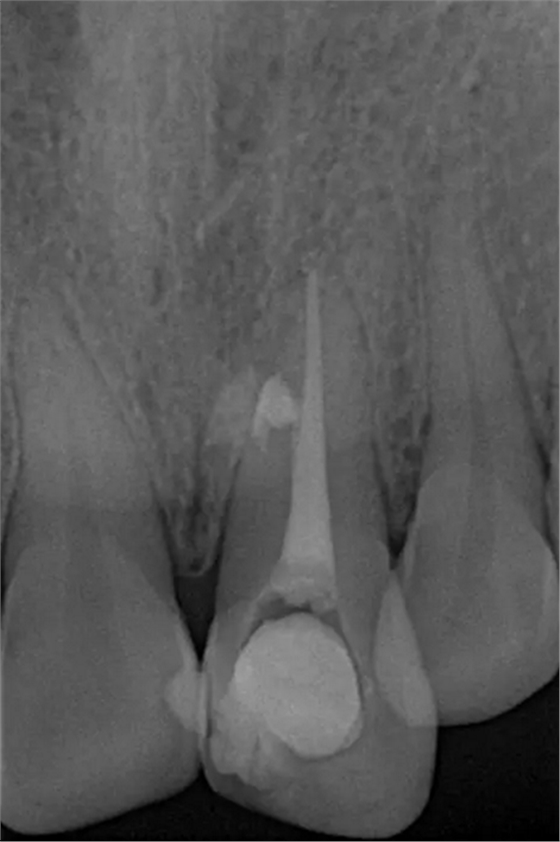

術(shù)后片

隨訪半年后,癥狀消除,熱牙膠根充